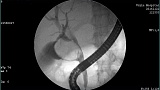

- Атлас